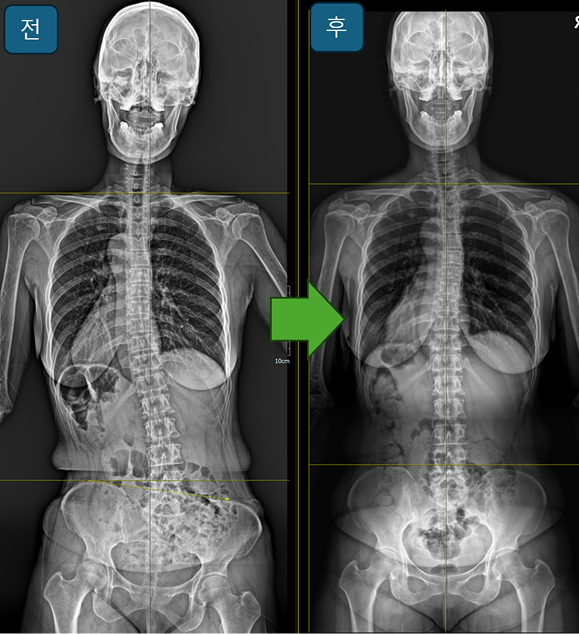

교정사례

조은정형외과의원의 깔창 교정 케이스